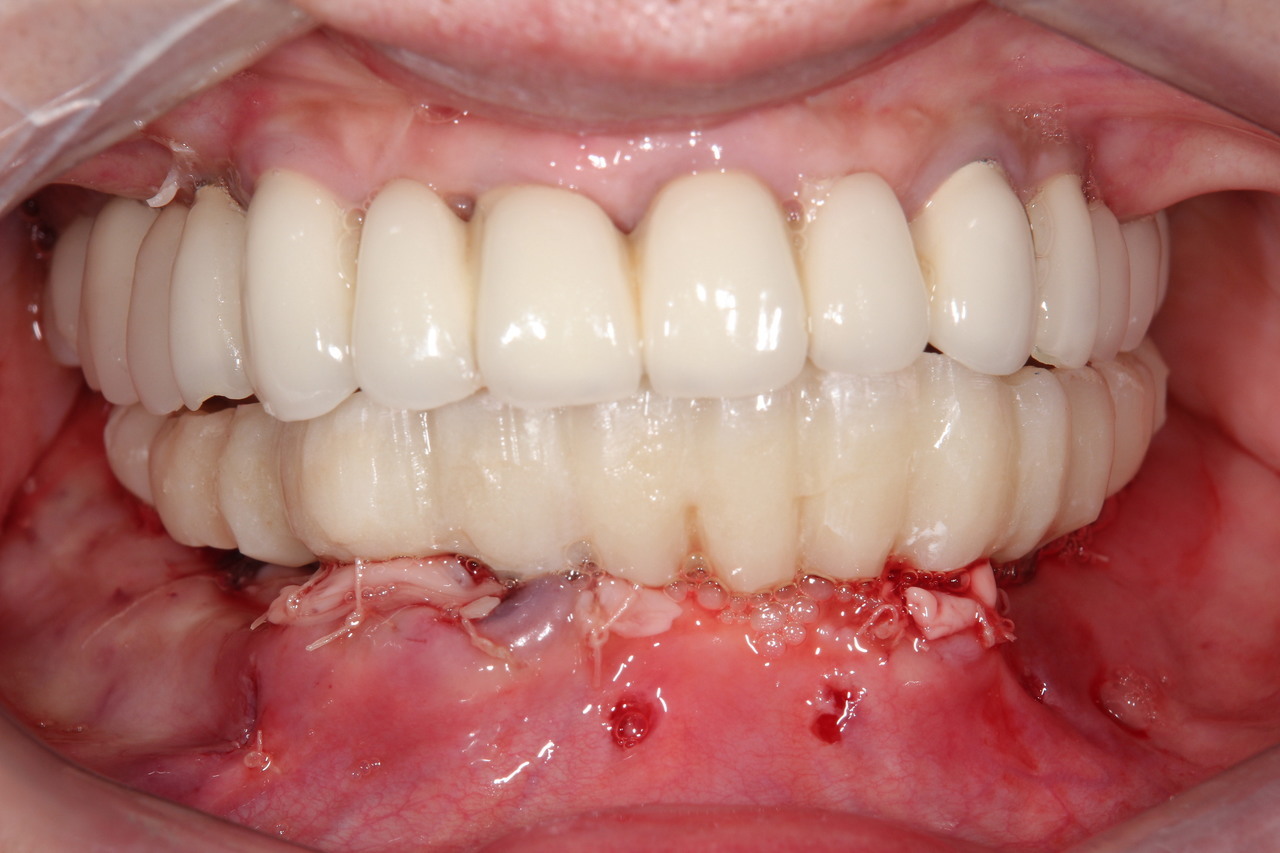

インプラント8本で14本の歯を並べたケース・仮歯代含む (函南町在住 女性

抜歯後、片顎8本のインプラントを埋入し、即日に仮歯を製作する事により、1日で片顎14本の歯を回復します。事前にインプラントを埋入する位置をCTによりシミュレーションし、埋入ガイド、仮歯を準備したうえで手術を行います。埋入ガイドにより、正確な位置にインプラントを埋入することができます。

仮歯装着①

インプラント埋入後、その日に用意していた仮歯を装着します。

仮歯装着②

仮歯をネジ止めして固定します。

これはまだネジ穴を塞いでいない状態です。

最終的な被せ物装着

インプラントがしっかり骨に定着したら、型取りをして、最終的な被せ物を製作し、装着します。